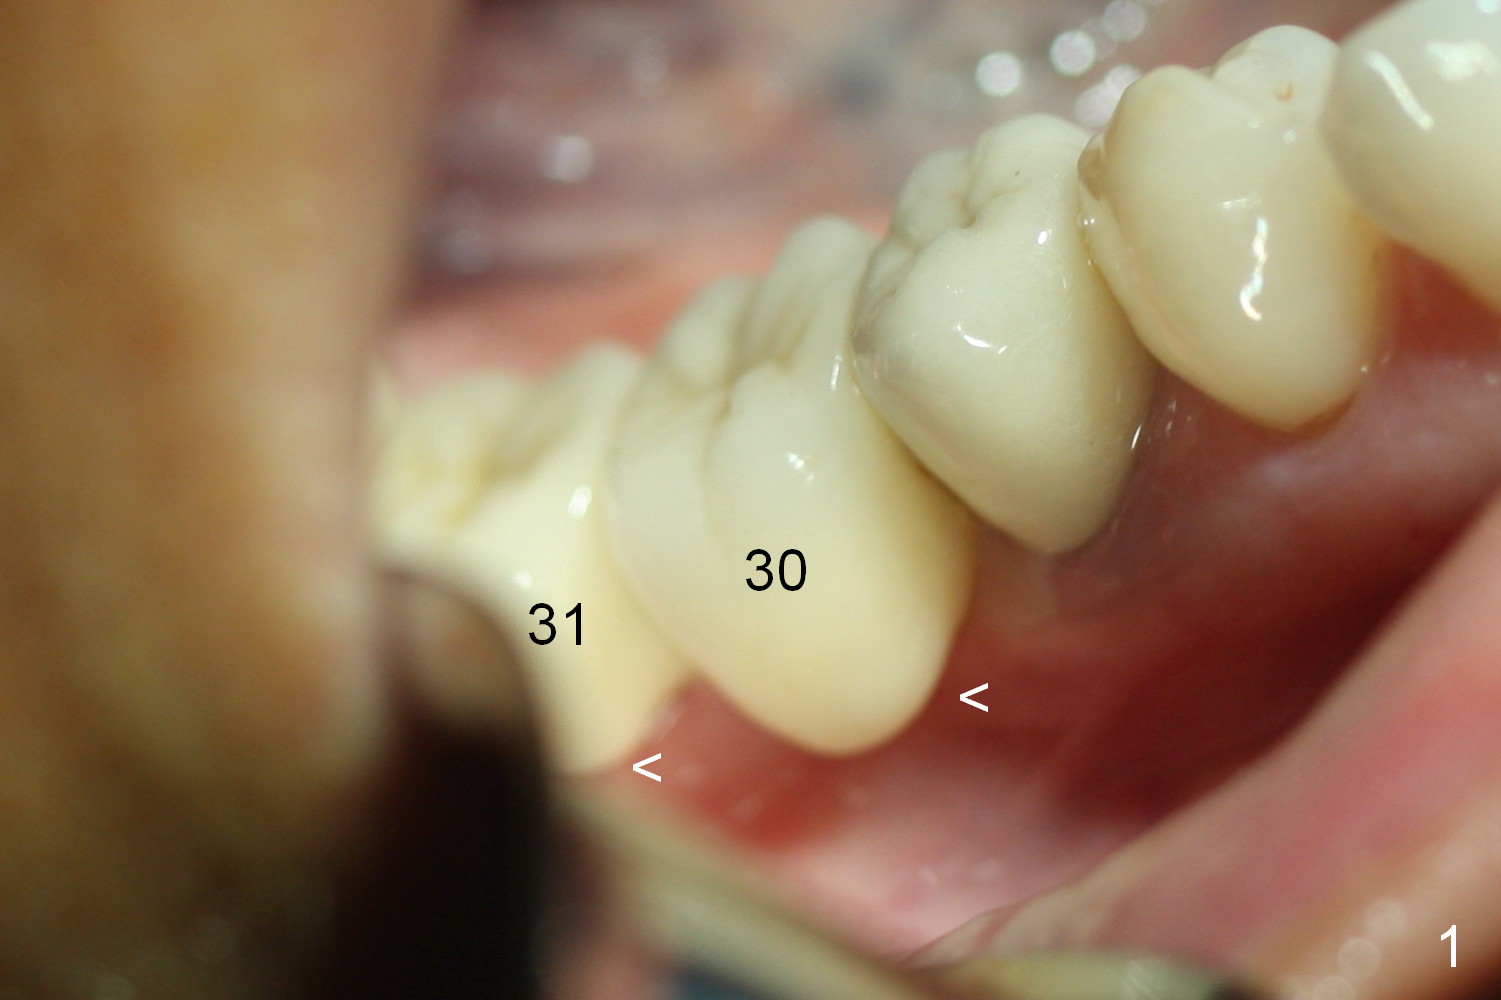

A preop photo shows different shape of pontics at #30 and 31 (Fig.1 <), suggesting different width of the edentulous ridge.  Two of 8 mm parallel pins are inserted for position and trajectory (Fig.2 (red dashed line: the superior border of the Inferior Alveolar Canal).  When they are removed from the osteotomy sites, the narrow ridge at #30 is shown (Fig.3).  A 3x12 mm 1-piece implant is placed at #30, while a 4.5x10 mm 2-piece one at #31 (Fig.4,5).  It appears that it is necessary to place an implant at #32, since the tooth #1 is present (Fig.5).  The suggestion is rejected by the patient due to finance.  After extraction of the tooth #32 and insertion of collagen plug, an immediate splinted provisional is fabricated to cover the #32 socket as well (Fig.6).  The provisional is modified (to remove the portion that covers #32 socket) 3-4 weeks postop.